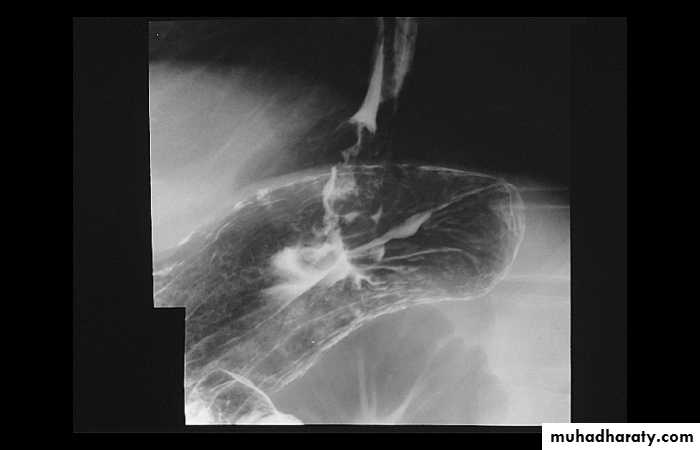

esophagography is unique among esophageal studies for assessing both morphology and motility. Barium esophagography remains the study of choice for characterization of esophageal strictures. Esophageal carcinoma may demonstrate a variety of appearances on barium esophagrams.

Annular Carcinoma

Narrowing :1-Constant.

2-Irrigular .

3-Variable length.

4- Shouldering sign.

5-Fistula (double tract).

6-Soft tissue shadow of the mass